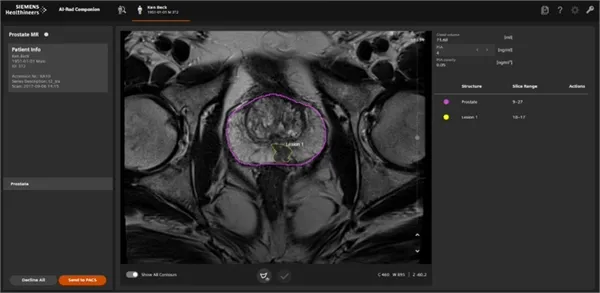

La imagen muestra una exploración por IA de una próstata. El AI-Rad Companion Prostate MR realiza una segmentación automatizada de la próstata para diferenciarla de otros órganos. El radiólogo marca y caracteriza manualmente las lesiones y otros objetivos que la IA ha encontrado. En esta imagen, la línea morada identifica la próstata mientras que la línea amarilla contornea una anormalidad, o lesión, que podría ser cancerosa. (Crédito: Siemens Healthineers vía Clínica Universidad de Navarra, España)